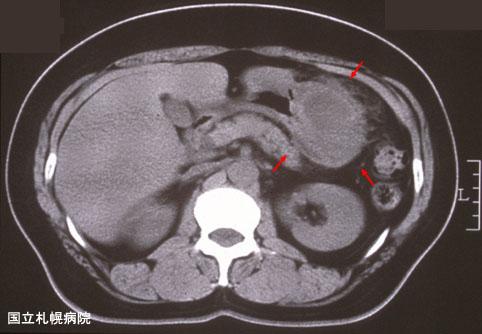

A case of an inflammatory tumor presenting as a gastric submucosal tumor.

Inflammatory or ulcerative disease / lesions/Others

Stomach/Body

CT

40 -